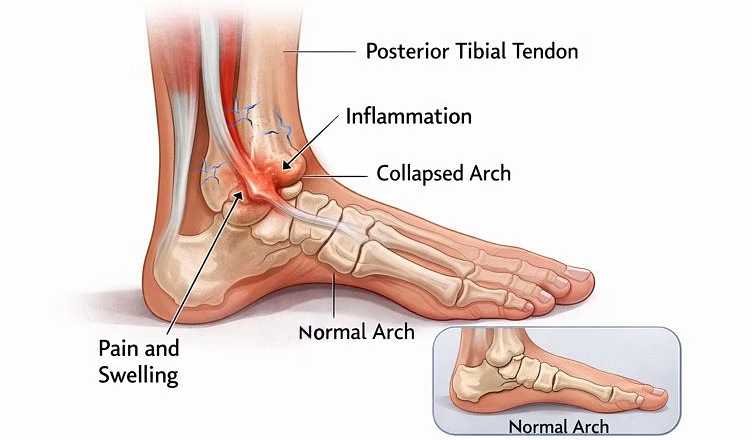

Flatfoot can be flexible (the arch reforms when non-weight-bearing or on tiptoes) or rigid (stiff and fixed). In adults, one of the most common causes of a painful, progressive flatfoot is posterior tibial tendon dysfunction (often referred to as progressive collapsing foot deformity). The posterior tibial tendon helps support the arch; when it becomes inflamed, stretched, or torn, the arch can gradually collapse, and the hindfoot can drift into valgus (heel rolling outward).

- Pain along the inside of the ankle/arch (often tendon-related)

- Pain on the outside of the ankle due to impingement as the heel drifts outward

- Swelling, fatigue, or a feeling of “giving way”

- Relieve pain and reduce inflammation or impingement

- Tendon procedures: cleaning (debridement) or reconstruction of the posterior tibial tendon; sometimes tendon transfer to support arch function

- Spring ligament or deltoid ligament reconstruction: when ligament support has failed